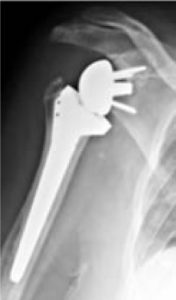

De omgekeerde schouderprothese

Als er naast slijtage van de schouder ook een onherstelbare peesscheur bestaat, wordt er gekozen voor deze schouderprothese. Bij deze schouderprothese worden de delen omgekeerd geplaatst: de beschadigde kom wordt vervangen door een bol en de beschadigde schouderkop wordt vervangen door een steel met een kom (zie afbeelding hieronder). Deze prothese wordt meestal geplaatst als de rotator cuff spieren afwezig zijn. De schouder kan dan bewogen worden door de grote schouderspier (Detoideus spier). Hierdoor kunnen meestal de kracht en bewegingsmogelijkheden van de schouder zoveel mogelijk worden hersteld.

Indien de schouderkop in meerdere stukken gebroken is, op een zodanige wijze dat deze niet meer hersteld kan worden, geeft dit ook een blijvend verlies van een belangrijk deel van de aanhechtende pezen. In dat geval wordt er voor een speciale omgekeerde schouderprothese voor fracturen gekozen.